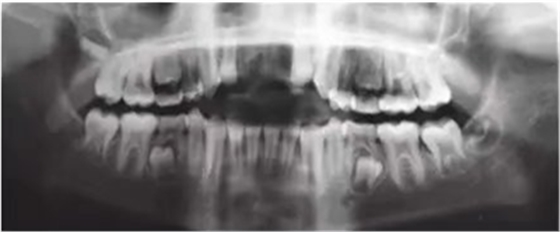

6個(gè)月后,移植牙的根尖片顯示治療期間沒(méi)有出現(xiàn)牙根吸收的影像?;颊邲](méi)有出現(xiàn)不適,沒(méi)有發(fā)生牙齦炎。在23個(gè)月期間沒(méi)有進(jìn)行任何修復(fù)完成治療,達(dá)到I類關(guān)系(圖5和圖6)。

圖5. 正畸后影像學(xué)檢查

圖6. 正畸后口內(nèi)照